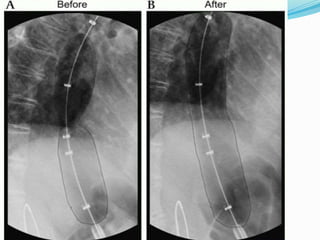

A 47-year-old female presented with 6 months of dysphagia and difficulty swallowing solid foods, as well as 4 months of odynophagia and weight loss of 2 kg over 6 months. Examinations and investigations including endoscopy, barium swallow, esophageal manometry and CT scan revealed achalasia cardia. The patient underwent balloon dilatation and will follow up every 6 months with barium swallow tests.